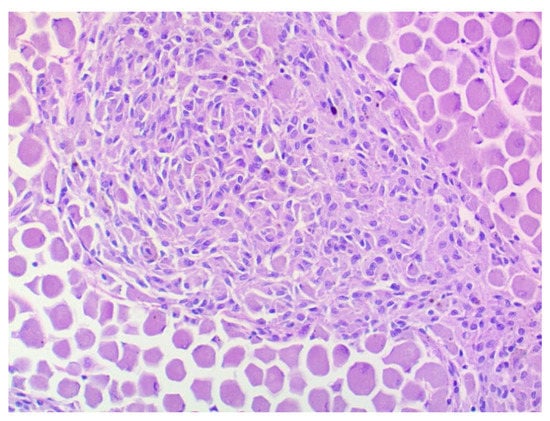

The histopathological investigation revealed a choroidal melanocytoma with partial infiltration of the sclera and optic disc, and perineural retrobulbar extension (Figure 5). The cross-section showed a diffuse infiltration with two different cell types: one plump, heavily pigmented population and a second spindle cell type of melanocytic cells. In the bleached sections (Figure 6), the two cell types showed a round to oval nucleus, respectively, and the majority of one nucleolus was visible. No significant atypia and very low mitotic activity, less than 4 mitoses in 10 high-power fields (HPF), were observed. The plump, pigmented cells could be found in the periphery of the optic nerve. No vascular invasion was found. The tumor bed biopsies confirmed retrobulbar spreading in one of the three specimens. There were pigmented cells without atypia, loosely interspersed and partly more densely packed between the skeletal musculature and the local adipose tissue.

Figure 6. Choroidal melanocytoma: a population of large round cells with a very broad cytoplasm at the edge, and a second spindle cell population with a smaller cytoplasm in the center of the image. No significant atypia or mitoses. Bleaching, 200× magnification.